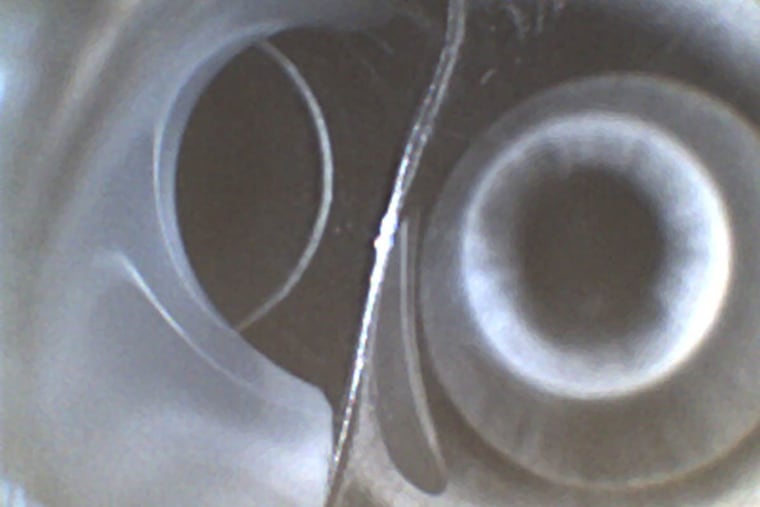

Researchers in Minnesota unexpectedly found cloudy, white fluid inside several colonoscopes and gastroscopes after they had been disinfected and deemed ready for use on the next patient.

No infections have been specifically linked to the drops thus far. The study only suggests that they could heighten the risk of contamination. "Finding residual fluid in scopes that should be dry would be troubling alone," said Cori Ofstead, the study's lead author. "The finding of fluid containing simethicone suggests we have more serious problems. It could explain why we are having more trouble getting these scopes clean."